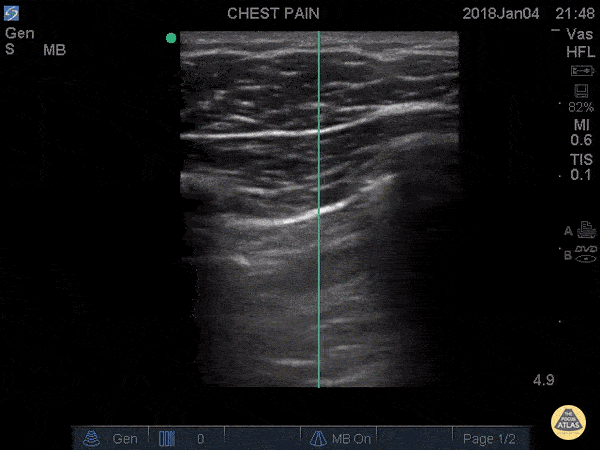

Trauma code to the waiting room... 20 y/o male stabbed to the left chest in the midaxillary line. Patient thrown in a wheelchair and pushed to the resuscitation room and POCUS performed immediately revealing this image: the lung sliding disappearing revealing an area without lung slide. Moved up one rib space to the apex, no lung slide at all. This junction of slide/no slide is the lung point and its pathognomonic for pneumothorax. It represents the exact point where air begins to separate the parietal from visceral pleura, aka the junction of where we normally see the "ants marching" or the "shimmering" aka the lung slide. This is highly specific. Don't be fooled when you see the sliding with decreased sliding around it. You're looking at a pneumothorax.